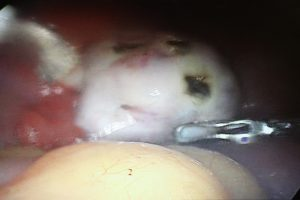

4-Polikistik over ameliyatı miktarı ve etkinliği artmış olan erkeklik hormonlarının (testosteron, dihidrotestosteron) etkinliğinin ve miktarının azaltılması ve insülin duyarlılığının artması sonucunda SHBG miktarını arttırarak etki gösteren bir tedavi seçeneğidir(78,79,80).